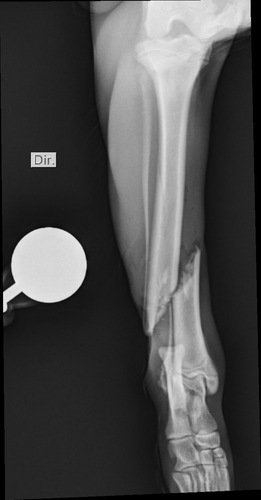

Tatu fugiu e foi atropelado, o motorista fugiu e não prestou socorro, ele teve 3 fraturas e terá que a realizar 3 cirurgias, fora exames e a internação na clínica  ver tudo

Tatu fugiu e foi atropelado, o motorista fugiu e não prestou socorro, ele teve 3 fraturas e terá que a realizar 3 cirurgias, fora exames e a internação na clínica